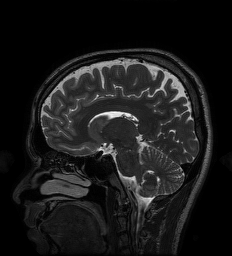

5.6 MRI Experiments

| Original/Mask | PNN | NN | MoDL | GDN2 | GDN1 | TNRD | TV |

| PSNR (dB) | 34.95 dB | 33.09 dB | 34.09 dB | 33.18 dB | 31.37 dB | 32.39 dB | 32.29 dB |

| Test Time (sec) | 16.3 sec | 5.5 sec | 14.3 sec | 5.7 sec | 3.1 sec | 4.0 sec | 349.2 sec |

In this section we provide results of multi-coil MRI reconstruction from undersampled measurements. Full training and test data is the data used for the experiments in [47], consisting of 12-coil Cartesian sampled k-space data of dimension with known coil sensitivity maps. The size of the training set is 360 such acquisitions across 4 subjects, with testing being performed on 40 images from one, separate subject who was not used for training. The sum-of-squares reconstruction is treated as ground truth. Further details of the data acquisition can be found in [47].

All experiments are for 4 undersampling, although we differ from [47] in that we train on a fixed k-space undersampling mask. The undersampling mask is fully sampled in the center 0.15 fraction of frequencies, with the remaining frequencies being sampled according to a random Gaussian pattern. The mask is visualized in figure 10.

For the MRI experiments we follow the precedent set by [47] in our choice of learned component, using only a simple five-layer convolutional network with 64 filters per layer and ReLU nonlinearities for all architectures other than TNRD. The TNRD architecture follows the architecture proposed in [33]. The Neumann network results presented here are for the preconditioned Neumann network (PNN), and the number of blocks for GDN, PNN, MoDL, and TNRD is fixed to be 5. The preconditioning operator in PNN is implemented through 10 conjugate gradient iterations, identically to [47]. We compare to GDN with the same initialization as NN (GDN1) and as PNN (GDN2) to study the effect of different initializations on GDN.

We observe that unrolled optimization approaches are advantageous in this setting compared to the more traditional TV-regularized reconstruction. Preconditioning, both to improve initialization as in GDN2, and incorporated into the architectures, as in PNN and MoDL, improves PSNR significantly in this setting.

A major benefit of learned reconstruction methods is their test time, which is displayed beneath the method name and PSNR in Figure 10. We note that all learned approaches reconstruct an order of magnitude faster than the agnostic TV approach. Although preconditioning incurs an additional cost in terms of test time, the performance increase is substantial for MoDL and PNN.